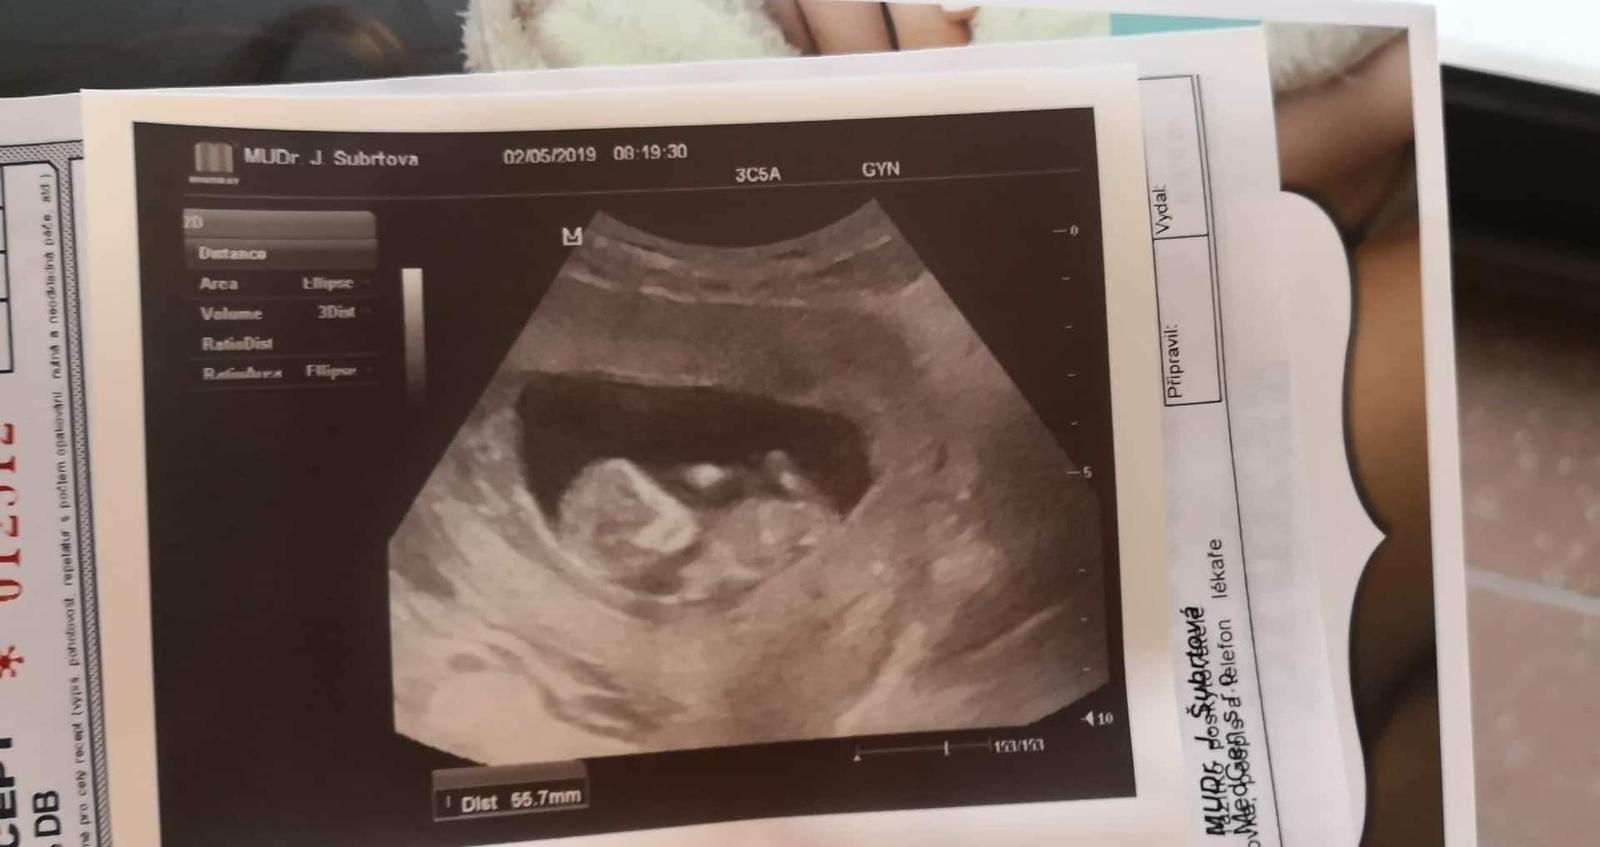

Ahoj holky, ta jsem se po X letech konečně poprvé zaregistrovala vždy jsem jen projížděl diskuze jako neaktivní člen, tak mam radost ze mohu byt konečně mezi Vami❤️jinak my mame termín 25.11-1.12 a jsme 11tt včera byla kontrola a odebrani krve na prvotrimestrální screening ktery nas čeká příští pátek, doktorka mi dokonce rekla i pohlaví což me trochu zarazilo, přiznám se ze jsem zadržovala slzy jelikoz jsem si přála vysněnou holčičku a na ultrz. Byl zvoneček 😄😄ale dnes jsem uz happy protože malej (4)bude mít bráchu a je to pro něj to nejlepší co může být ❤️